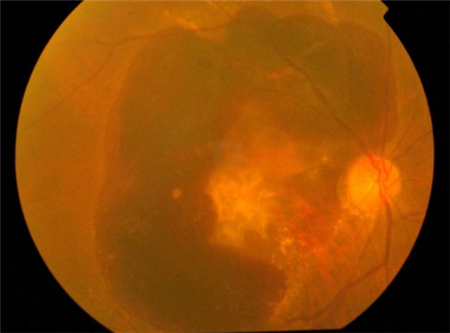

雖然激光有一定的正面作用,但如果使用不當(dāng)也是非常危險的。使用激光筆直接照射眼睛時,激光筆發(fā)射出的激光會直接進(jìn)入眼內(nèi)到達(dá)視網(wǎng)膜部位,由于激光筆的熱效應(yīng),有可能會灼傷視網(wǎng)膜,造成視網(wǎng)膜的中心“黃斑區(qū)”受損。輕則灼傷感光細(xì)胞,重則可能導(dǎo)致黃斑裂孔,造成難以恢復(fù)的視力損害。

所以即使是激光治療當(dāng)中,為了保護(hù)患者眼睛,我們的眼科醫(yī)生也會盡量避開黃斑中心。而我們在生活當(dāng)中,更不可使用激光筆隨意照射自己以及他人的眼睛。